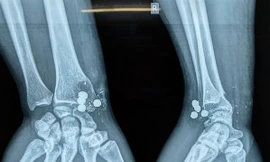

Nghịch súng kíp, nam thanh niên bị 5 viên đạn bắn trúng tay

TPO - Đến nhà bạn chơi, thấy súng kíp gác ở mái nhà, anh T. kéo xuống xem thì súng nổ, 5 viên đạn bắn vào cổ tay thanh niên này. Tại bệnh viện, các bác sỹ đã phẫu thuật lấy các mảnh đạn ra.